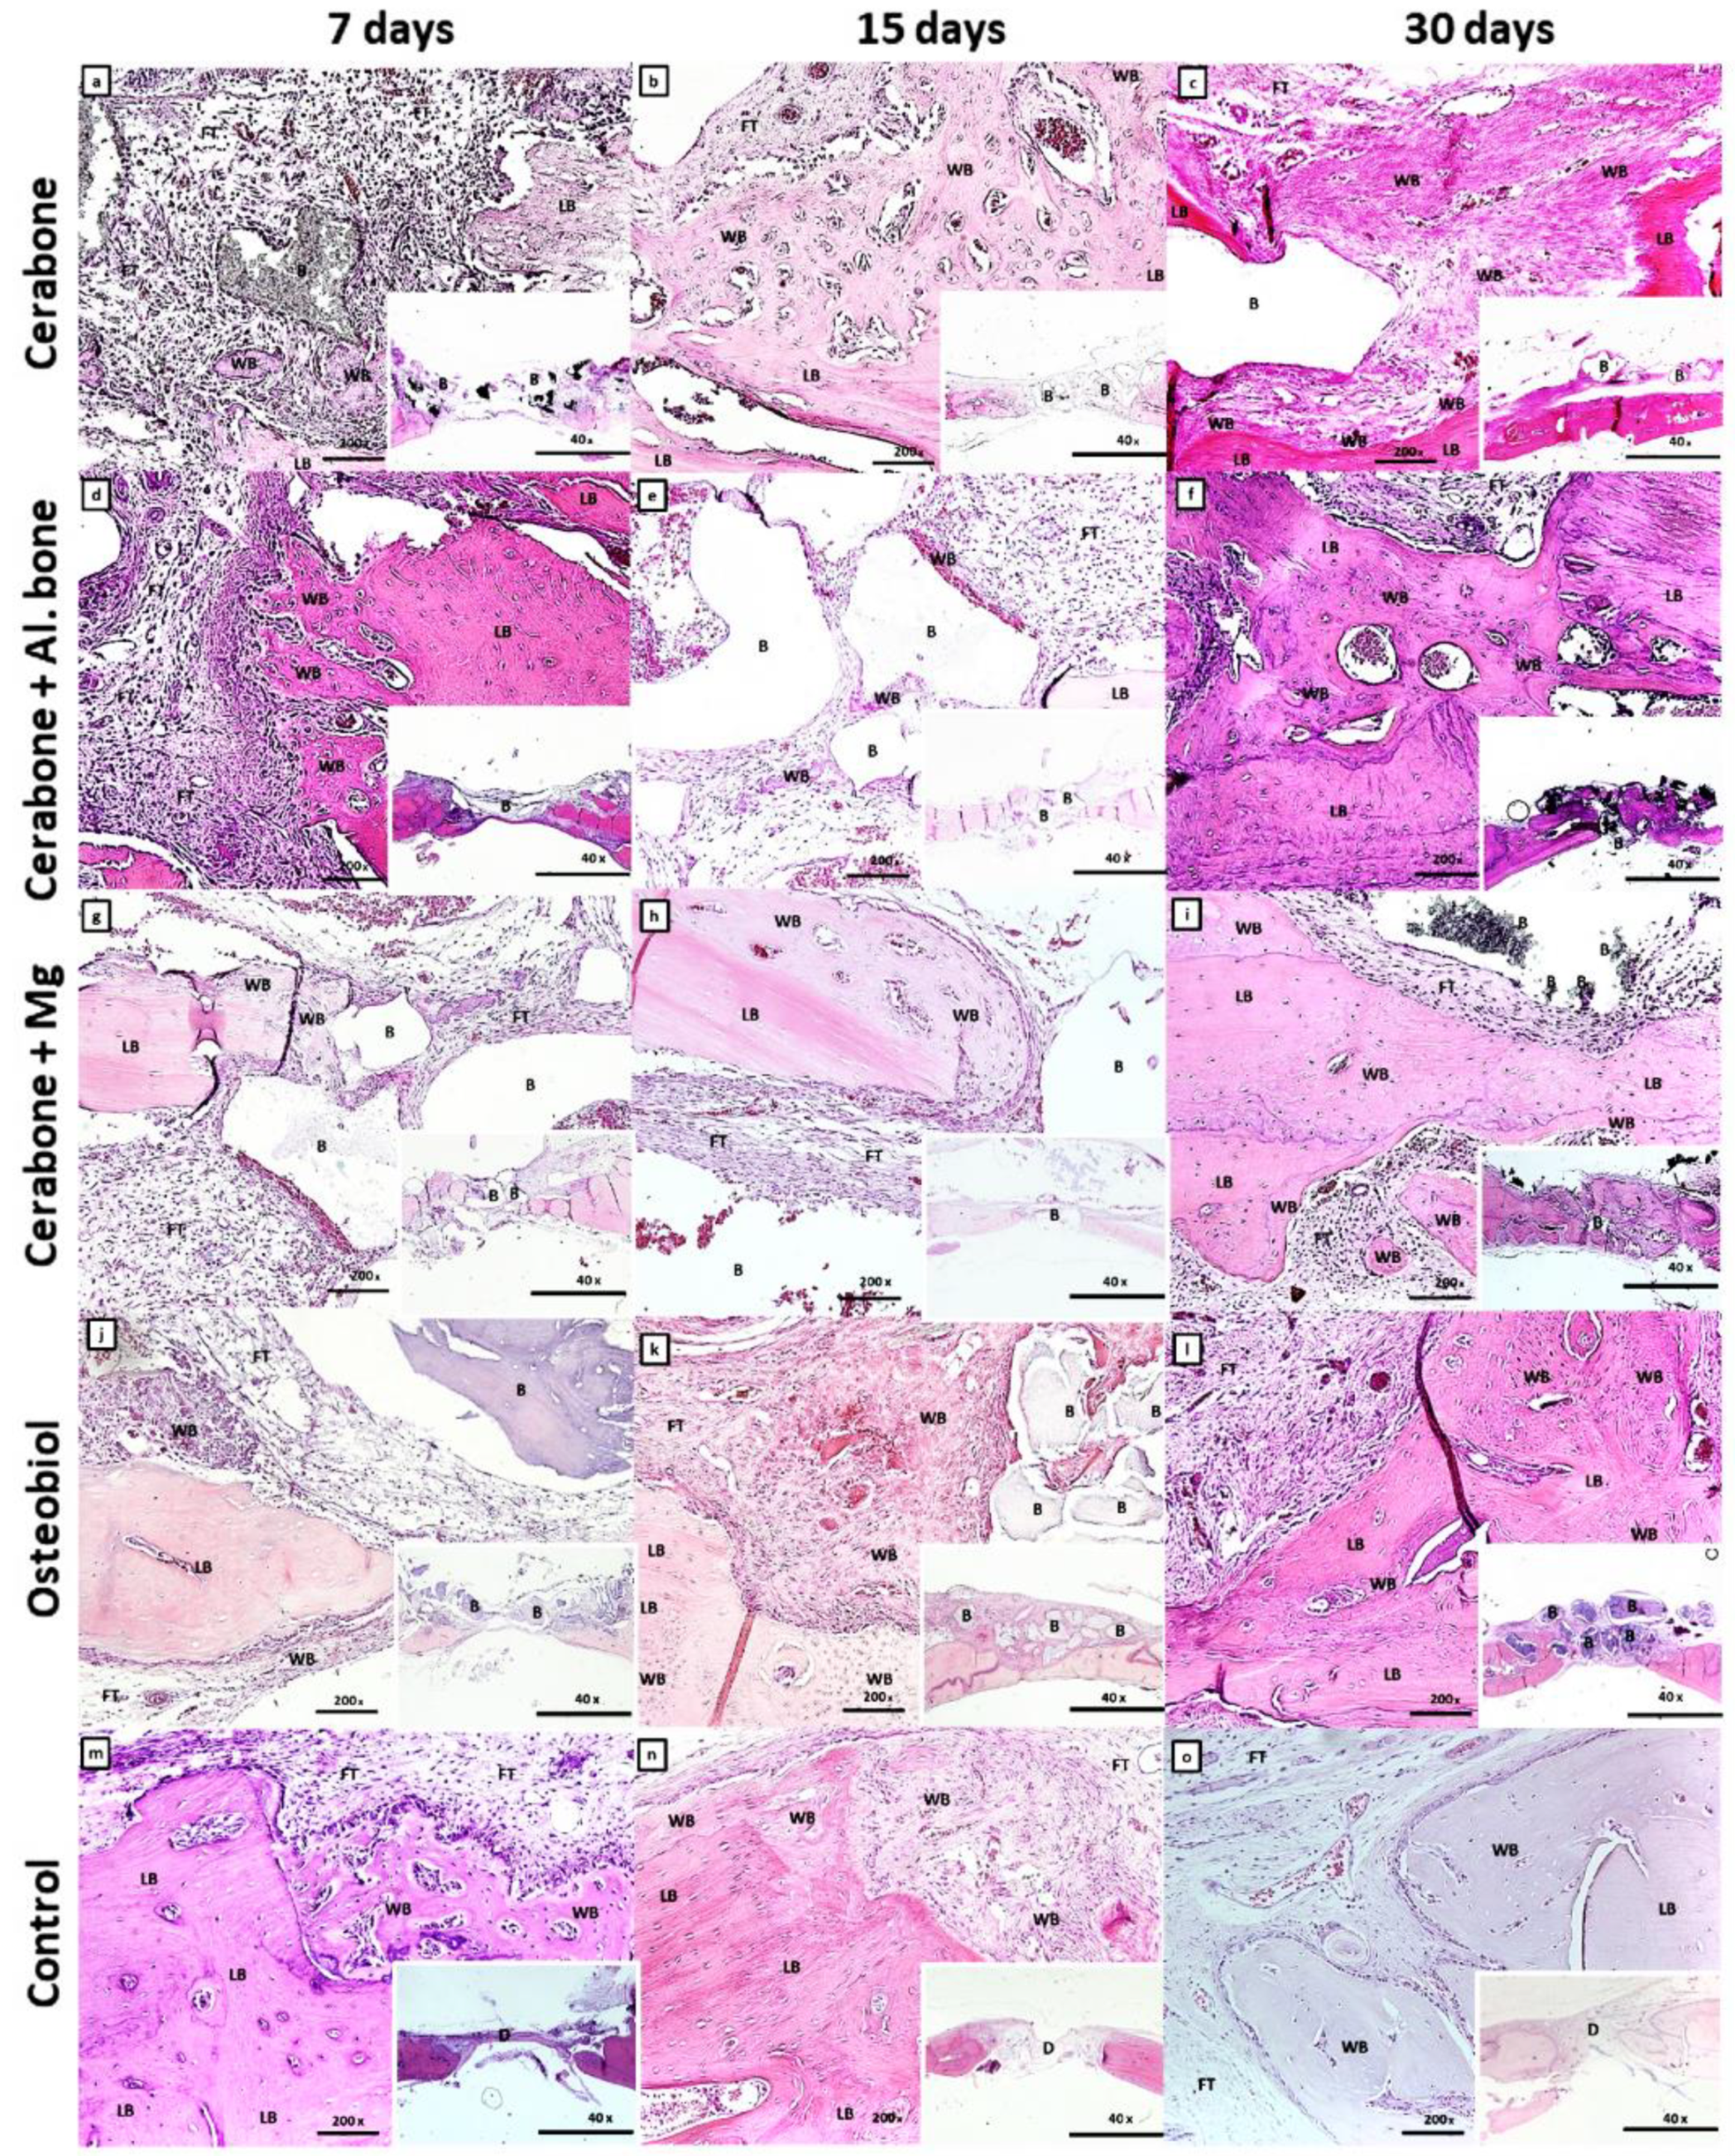

2.2. Histology and Immunohistochemistry